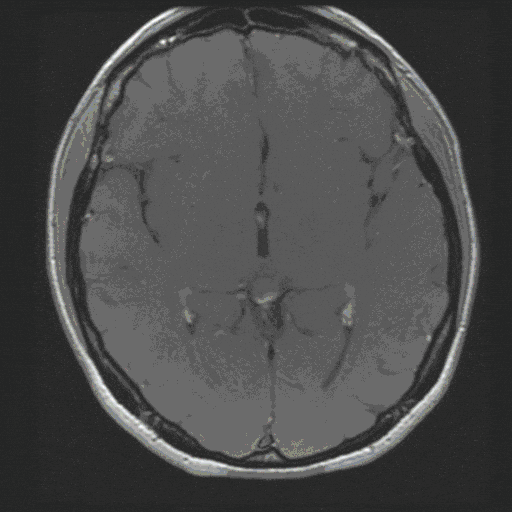

Acoustic Neuroma

Acoustic neurinoma (actually vestibular schwannoma) is a benign tumor of the cerebellopontine angle. It can grow considerably in size due to its slow growth, thereby threatening the brain stem and its cranial nerves.